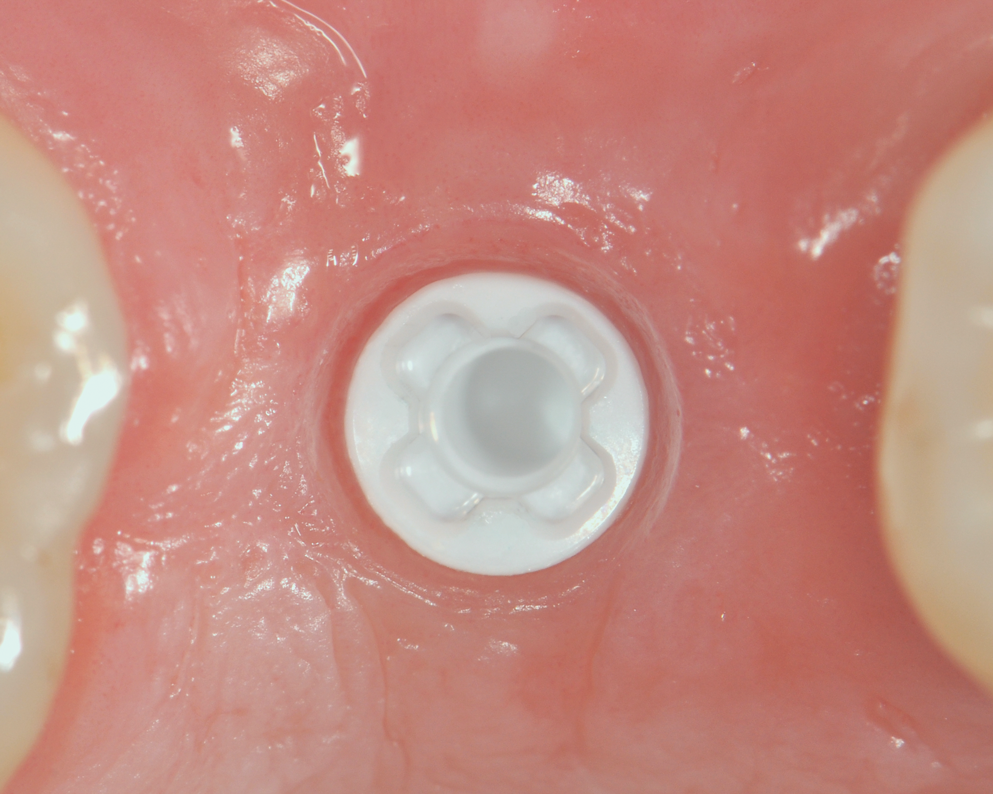

While more scientific evidence showing a lower tendency toward peri-implantitis may still need to be provided for ceramic implants, the essential argument for these implants based on clinical experience is the excellent and almost consistently inflammation-free peri-implant soft-tissue condition (Figure 3).

Fig 3. Soft tissue with zirconia implant free of inflammation.

Figure 3